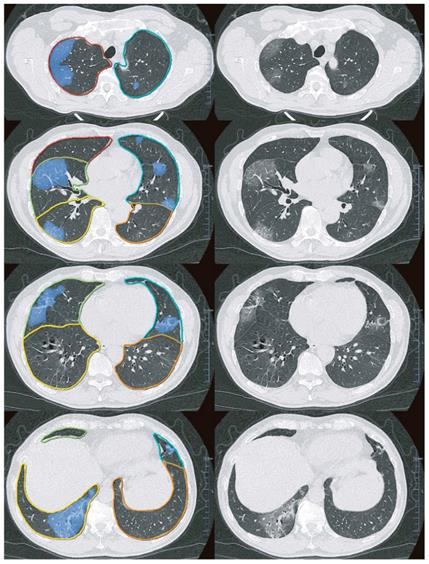

We performed lung segmentation, lesion extraction and labeling, and volume calculation using a dedicated multi-task deep learning algorithm developed for pulmonary pneumonia (Beijing Deepwise & League of PhD Technology Co.Ltd, China) [18]. A 3D U-Net was introduced for pixel-level classification with a large-scale annotated data. The system's accuracy was guaranteed by engineering approach and manually checked by a radiologist (Y.C.W) with > 10 years of experience in chest imaging. Technical details and the accuracy of the AI method are showed in Supplementary Methods. Figure 2 shows an example of pulmonary lobe and opacities segmentation.

Figure 2

Examples of Pulmonary lobe segmentation and opacity segmentation. Left: Pulmonary lobes and opacities segmentation; Right: original images.

Theranostics Image

First, we segmented each lung lobe and the bilateral lungs and calculated the volume. Subsequently, we labeled the GGO and consolidation lesions in the corresponding lobes using the well-trained AI algorithm and computed the volume. Based on these parameters, we calculated the number of involved lung lobes and the lesion volume percentage in each lobe (right upper lobe [RUL], right middle lobe [RML], right lower lobe [RLL], left upper lobe [LUL], and left lower lobe [LLL]) and the whole lung. The RUL, RML, and LUL were defined as the upper lung while the remaining lobes were defined as the lower lung. Subsequently, to describe the HU distribution, we measured the volume of several opacities using the following cutoff HU values: -200, -400, and -600 HU, and calculated the percentage of each HU subsection volume in the whole lesions. We described the lesion location and distribution as the median distance from every lesion voxel to pulmonary pleurae in the upper and lower lung with a lower distance indicating subpleural area distribution.